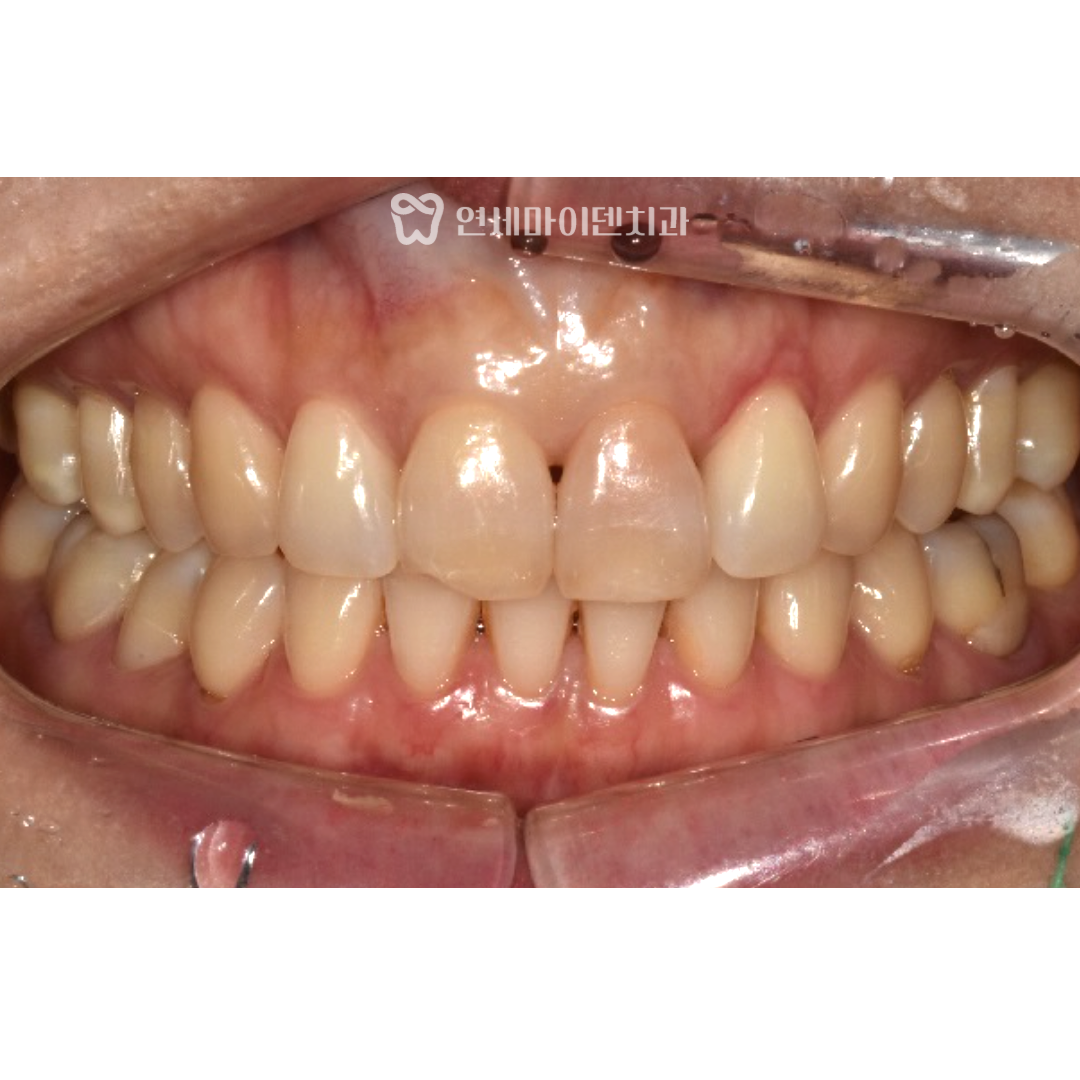

석회회로 변색된 앞니 실활치 미백 전후 비교

치료 불가능 진단까지 받았던 앞니를

신경치료와 실활치 미백 3회만으로 해결하였습니다.

치료 전 변색되어 어두웠던 앞니는

확연히 밝아져서 옆 치아와도 차이가 잘 느껴지지 않습니다.

또한 외상으로 일부분 깨져 있던 앞니는

레진 수복을 통해 자연스럽게 복원하였습니다.